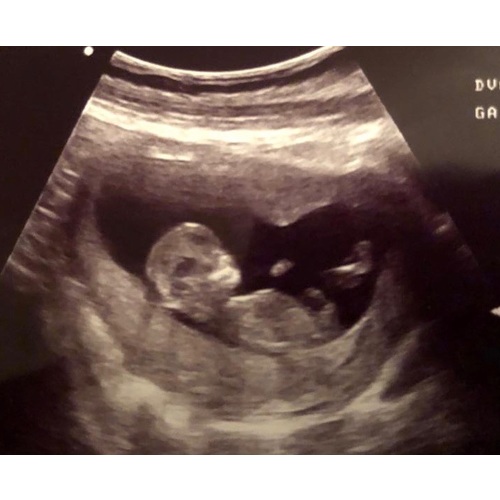

Dit was mn 12 weken echo 😅

Nu al eigenwijs ding dus ze zal wel echt van mij zijn vrees ik